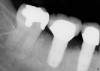

A review of the published literature on the subject of implant removal techniques showed only seven articles that satisfied the inclusion criteria (Table 1).7-13 These included the use of high/low-speed burs, elevators, trephines, and piezo surgical techniques. Based on these articles and clinical data from the Implant Database an evaluation of the advantages and disadvantages of using each of these implant removal techniques was made (Table 2). In addition, examples are presented depicting the various techniques used for implant removal (Figure 1 through Figure 13).

There are several sizes of trephines available that correspond to various implant diameters (Figure 8, Figure 9, Figure 10 and Figure 11). The smallest effective size trephine should be selected to avoid collateral damage to the neighboring bone, teeth, and/or implants. The internal diameter of the trephine needs to be slightly larger than the implant to avoid engaging the implant body. The preferred speed to use a trephine is 1,200 rpm to 1,500 rpm with copious irrigation. This technique is one of the most invasive options for implant removal. Fatigue fracture of the mandible after the use of a trephine bur has been reported.25 Osteomyelitis is another complication that may occur following explantation with a trephine bur, particularly if bone is overheated.26 Thus, trephine burs are only indicated when absolutely necessary, and the retrieval procedure should be carefully planned and performed under copious irrigation with cooled saline.26 As previously stated, if the crown and abutments are present, it is essential that they are cut off and/or removed prior to trephine use. This allows for use of the smallest diameter trephine (Figure 9, Figure 10 and Figure 11). Oftentimes only the coronal half of bone around the implant needs to be removed to loosen the implant, at which point elevators, forceps, and, where possible, torque drivers may be employed as part of a combination technique, as described in the following section.